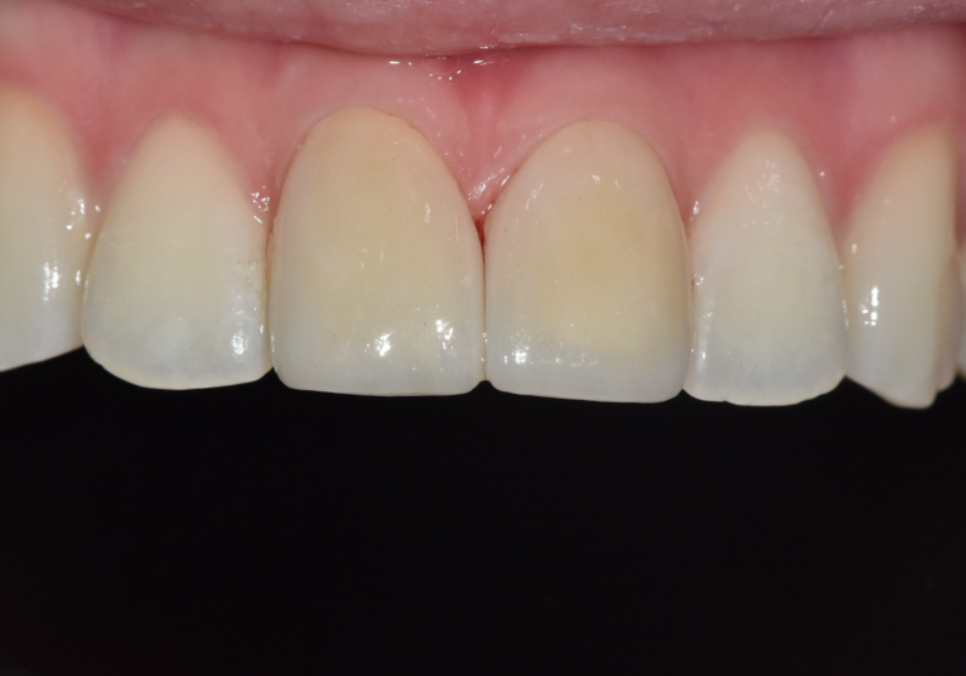

250410 절단교합으로 인한 앞니 레진 깨짐, 교정 없이 해결한 사례

250203(전) 250410(후)

최종 라미네이트를 부착한 모습입니다.

· 양쪽 앞니 길이가 가지런해지고

· 앞으로 뻗어 보이던 느낌도 자연스럽게 완화되고

· 절단교합에서도 힘을 덜 받도록 안정적인 공간이 확보되었습니다.

제가 계획했던 대로 라미네이트가 제작되어

저 또한 뿌듯했던 것 같습니다.